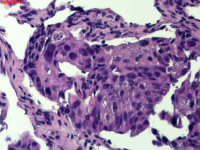

性别

男

年龄

40岁

临床诊断

肺癌?

一般病史

增强CT提示右肺中叶粘液栓;气管镜见右肺中叶外侧段新生物,考虑恶性可能。

图4

鳞状细胞癌